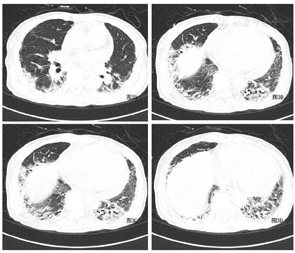

实验室检查:血气分析(FiO2:40%):pH7.416, PaO2:117.3mmHg(氧合指数:293),血常规:白细胞:4.50×109/L;中性粒细胞占:91.8%;淋巴细胞占:5.4%。血红蛋白:144g/L;血小板:273×109/L;心肌酶:肌酸激酶219.4 U/L,肌钙蛋白I 0.09ug/L,肌红蛋白41.0ug/L;乳酸脱氢酶490.5U/L;血沉:65mm/h;血清铁蛋白:1788ng/mL。抗核抗体:1:100,胞浆颗粒型,肌炎谱:抗MDA5-IgG(++)、抗Ro52-IgG (+++);胸部高分辨CT(HRCT)示:双下肺分布实变影,伴有肺容积缩小(图1)。

甲泼尼龙500mg×3天,逐渐减量(250mg×3天、160mg×3天、80mg×5天);环磷酰胺0.8gqw×2次;余予以全覆盖抗感染以及吡非尼酮600mg tid /d抗纤维化治疗。患者经过治疗后气促症状好转。患者于9月20日出现右侧大腿及臀部疼痛,未见红肿,皮温不高,无压痛。9月21日出现腹痛,压痛及反跳痛明显。急查血常规:红细胞:2.8*1012/L,血红蛋白:86g/L;凝血功能:PT:14.2秒、APTT:50.1秒、纤维蛋白原1.76g/L。综合上述临床表现,不排除腹腔出血可能性,行床旁B超提示腹膜后混合回声区,不排除脓肿或血肿。为进一步明确诊断,于当日申请急诊腹部CT,提示右侧腹膜后及右侧腹直肌多发血肿,周围脂肪间隙及腹膜增厚(图2)。请介入科会诊后建议介入治疗,因患者一般情况差,家属拒绝进一步治疗自动出院后随访患者死亡。